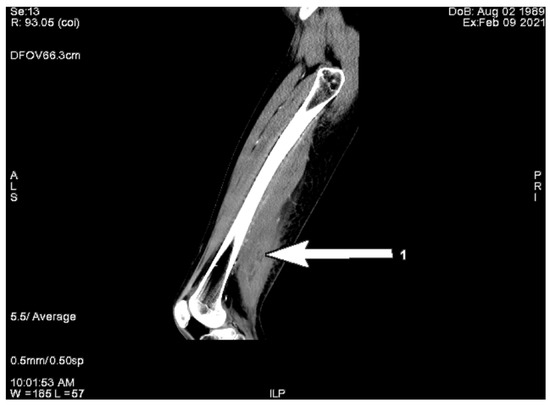

The decision of muscle biopsy for histopathological examination was made. The biopsy demonstrated diffuse areas of muscle necrosis and edema with a focal phenomenon of extravasation of blood. Light microscopy showed phagocytosis of necrotic muscle fibers with dispersed mononuclear cell infiltration. The presence of areas of granular tissue, early loose fibrotic tissue, and focal muscle fiber regeneration with lymphocytic infiltration was observed (Figure 3). Treatment involving bed rest and acetylsalicylic acid administration was introduced with subsequent improvement. The patient remained asymptomatic and was followed up as an outpatient.

To exclude other inflammatory problems, such as myositis or rhabdomyonecrosis, or amyotrophy, we decided to take a histopathological biopsy, which demonstrated diffuse muscle necrosis, edema, mononuclear cell infiltration, and local muscle fiber regeneration. The diagnosis of DMI was made after biopsy and histopathological evaluation of samples.

Figure 3. Histopathological presentation. (A) Areas of muscle necrosis and edema with extravasation of blood (HE, ×100). (B) Necrotic muscle fibers with focal replacement of necrotic fibers by loose fibrotic tissue (HE, ×200). (C) Early fibrotic tissue with mononuclear cell infiltration (HE, ×200). (D) Signs of muscle fiber regeneration with scanty lymphocytic infiltrates (HE, ×100).